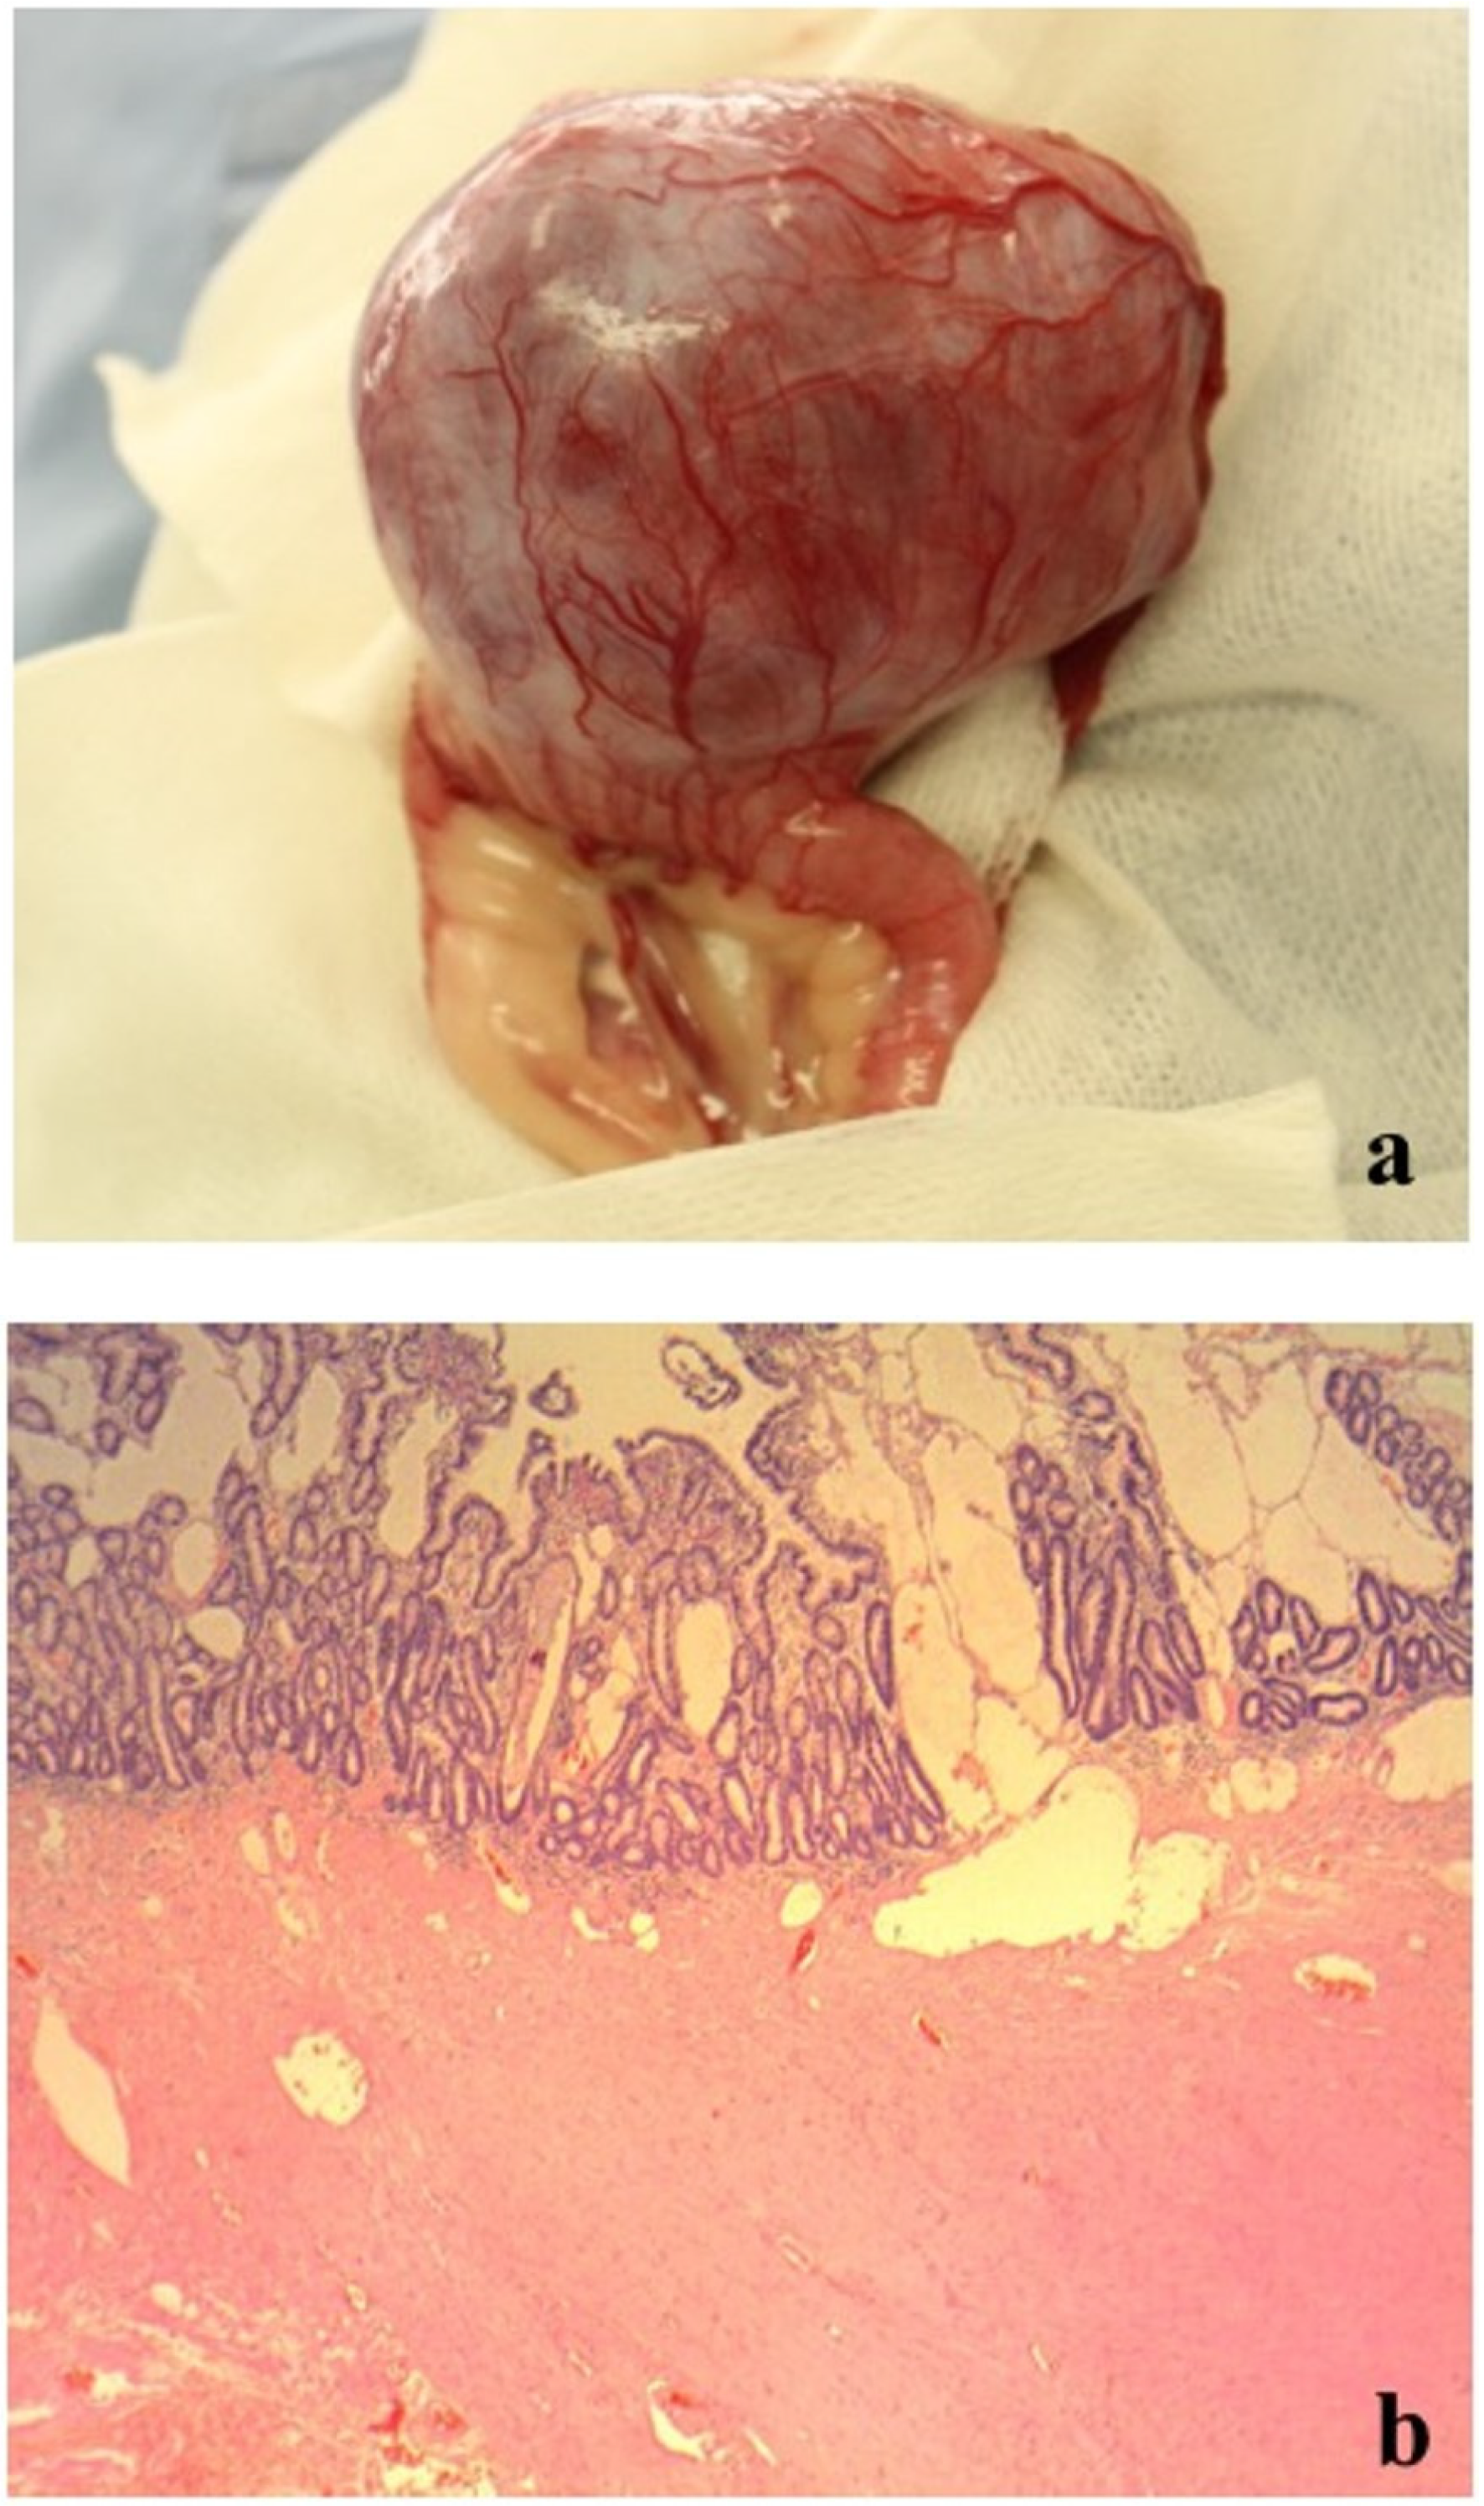

On day 2, an additional blood test performed before surgery revealed normal levels of total bile acid (5.0 μmol/L; RI, 0–15.3) (IMMUNO AU10V; FUJIFILM Corporation, Tokyo, Japan), prothrombin time (8.1 s; RI, 7.4–8.4), activated partial thromboplastin time (17.1 s; RI, 12.0–24.0), fibrinogen concentration (185 mg/dL; RI, 150–350) (COAG2; Wako, Osaka, Japan), and increased D-dimer concentration (53.9 μg/mL; RI, <2.0) (SpeLIA; Precision System Science, Chiba, Japan). All examinations were performed in our veterinary hospital. Anesthesia for laparotomy was introduced using propofol (Propoflo; Zoetis, Tokyo, Japan) and was maintained using isoflurane (Isoflurane for animal, Intervet, Tokyo, Japan). Atropine (Atropine sulfate injection; VEDECO, Missouri, USA), midazolam (Dormicum; Astellas, Tokyo, Japan), and butorphanol (Vetorphale; Meiji, Tokyo, Japan) were administered as pre-medications. Physiological saline (Otsuka normal saline; Otsuka, Tokyo, Japan) supplemented with 5% glucose (Otsuka glucose injection; Otuka, Tokyo, Japan) was administered as a fluid during laparotomy. The intraperitoneal mass (9 × 7 × 5 cm) originated from the jejunum, protruding from the serosal surface (Figure 2a). Hemoperitoneum and bleeding from the mass were not observed (Figure 2a). There were no findings of metastasis to other organs and the macroscopic appearance of the liver was normal. The portion of the jejunum harboring the mass was resected, and end-to-end anastomosis was performed. Full-thickness biopsy of the proximal jejunum and liver were performed simultaneously. Joint aspiration was performed to rule out systemic lupus erythematosus (SLE) at the time of surgery and revealed normal fluid levels. Postoperatively, intravenous infusions of acetic acid Ringer’s fluids (Soldem 1; Termo, Tokyo, Japan), meloxicam (0.2 mg/kg (0.09 mg/lb), subcutaneous injection (SC) (Metacam; Boehringer Ingelheim, Tokyo, Japan) for pain relief, cefalexin (20 mg/kg (9.1 mg/lb), SC, q 12 h) (Cefalexin; Nichi-iko, Toyama, Japan) for prevention of postoperative infection, and dalteparin Na (Fragmin 100 U/kg (45.4 U/lb), SC, q 12 h) (Nichi-iko, Toyama, Japan) for prevention of thrombus were administered.

The histopathological examination of the surgically resected mass revealed a mild atypical monomorphic proliferation of non-epithelial cells, exhibiting a spindle shape with abundant eosinophilic cytoplasm and resembling smooth muscle. Tumor cells were classified as malignant based on anisonucleosis, the increased nuclear–cytoplasmic ratio, and the presence of prominent nucleoli (Figure 2c). These findings indicated leiomyosarcoma. The mass had developed in the extraluminal space of the intestinal tract (Figure 2b). However, there was no transmural invasion of the tumor in the mucosa. Moreover, no intestinal bleeding was detected, but the lymphatic vessels on the mucosal surface were dilated (Figure 2b). In the jejunum proximal to the tumor, lymphangiectasia without any inflammatory changes was observed. In the liver, multifocal necrotic foci with infiltration of neutrophils and macrophages and bleeding were observed. We could not confirm whether these histopathological findings were caused by transient hypoxia due to anemia or whether they existed previously. All pathological examinations and subsequent diagnoses were confirmed by board-certified veterinary pathologists at commercial laboratories.

Figure 2. Macroscopic and histopathological findings of the surgically resected mass. (a) Macroscopic findings: The mass protruded from the serosal surface of the jejunum. (b) Histopathological findings (low-power field): The mass was located in the extraluminal space of the intestinal tract, but there was no transmural invasion of the tumor in the mucosa. No intestinal bleeding was detected, and lymphatic vessels on the mucosal surface were expanded. (c) Histopathological findings (high-power field): The mass revealed a mild atypical monomorphic proliferation of non-epithelial cells, exhibiting a spindle shape with abundant eosinophilic cytoplasm and resembling a smooth muscle. Tumor cells were classified as malignant based on anisonucleosis, the increased nuclear–cytoplasmic ratio, and the presence of prominent nucleoli.